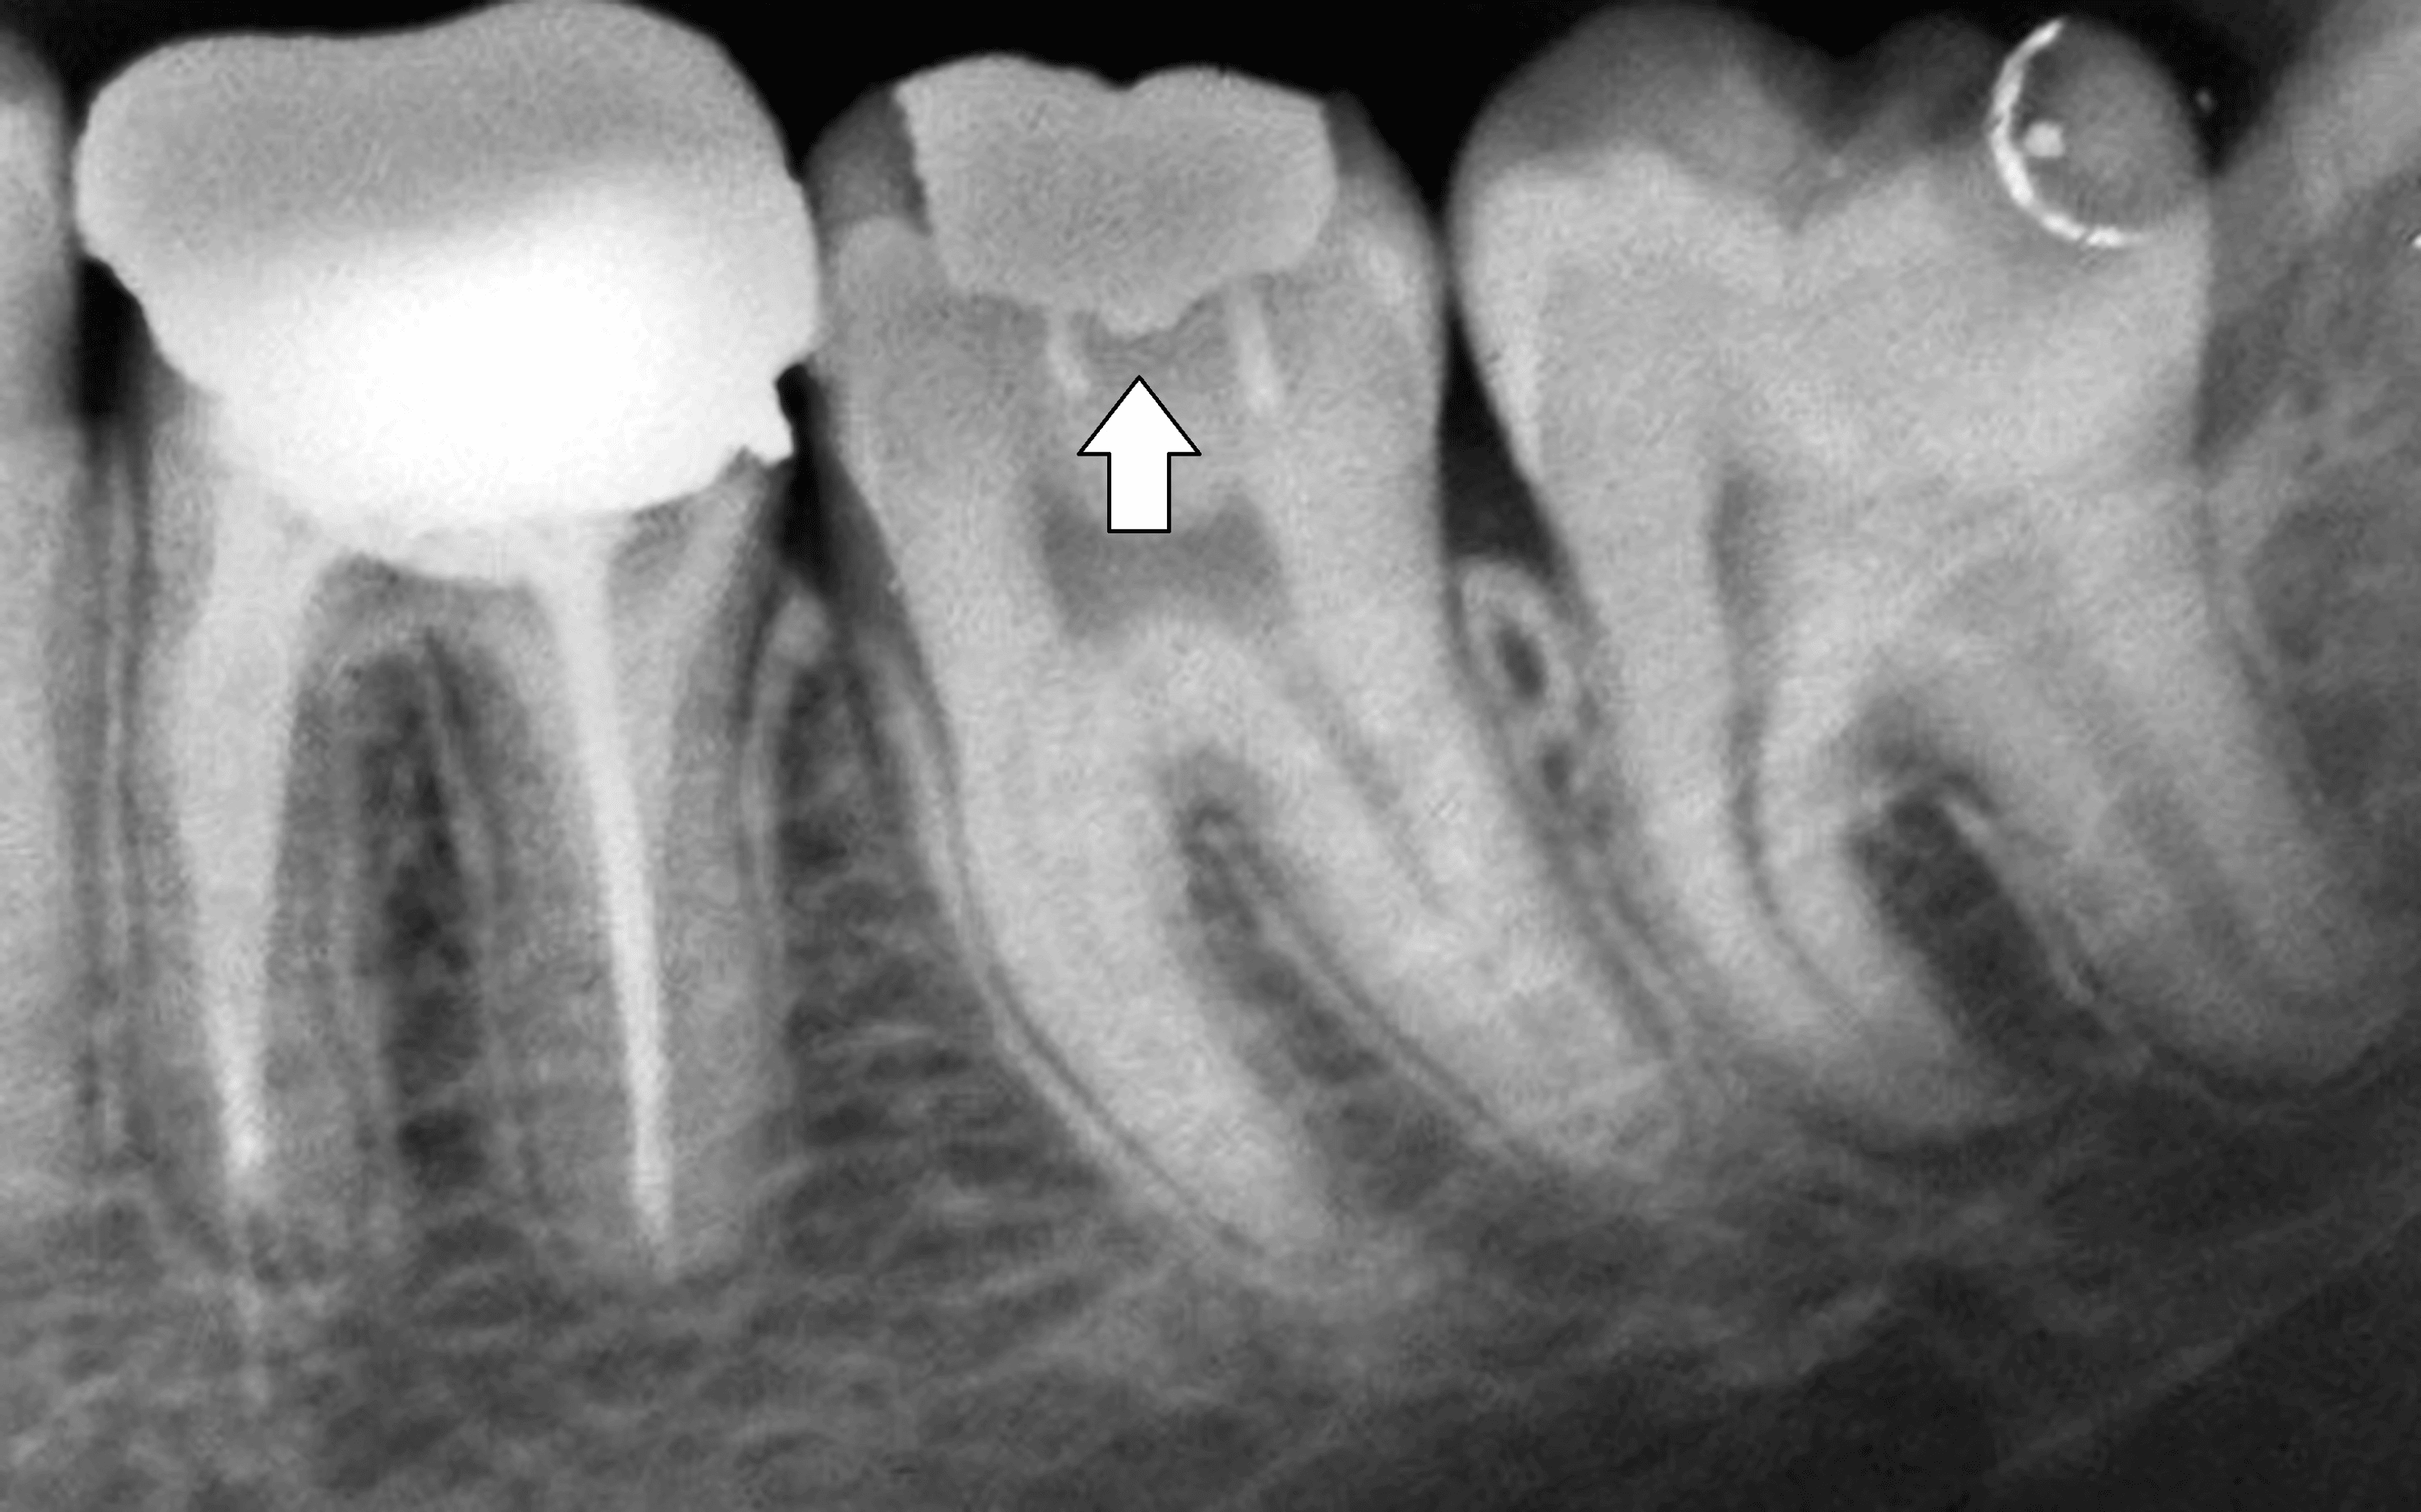

Pin Retained Core Core buildup is indicated for teeth with significant loss of coronal tooth structure due to caries or trauma in which insufficient. However, as the canal becomes more round, the need for accessory antirotation increases. Pin retained restorations defined as any restoration which requires the placement of one or more pins in dentin to provide to adequate resistance and retention form to the restoration. Peripheral distribution of retention and. Routine pin placement and addresses the following issues — removal of existing restorations, the need for a core, core materials, core retention,. Core buildup is indicated for teeth with significant loss of coronal tooth structure due to caries or trauma in which insufficient.

Pin Retained Core . Routine pin placement and addresses the following issues — removal of existing restorations, the need for a core, core materials, core retention,. Core buildup is indicated for teeth with significant loss of coronal tooth structure due to caries or trauma in which insufficient. However, as the canal becomes more round, the need for accessory antirotation increases. Pin retained restorations defined as any restoration which requires the placement of one or more pins in dentin to provide to adequate resistance and retention form to the restoration. Peripheral distribution of retention and.